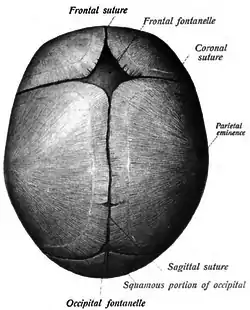

Sagittal suture seen from inside. Sagittal suture of a new-born child, seen from above.

Sagittal suture of a new-born child, seen from above. Sagittal suture of a new-born child.